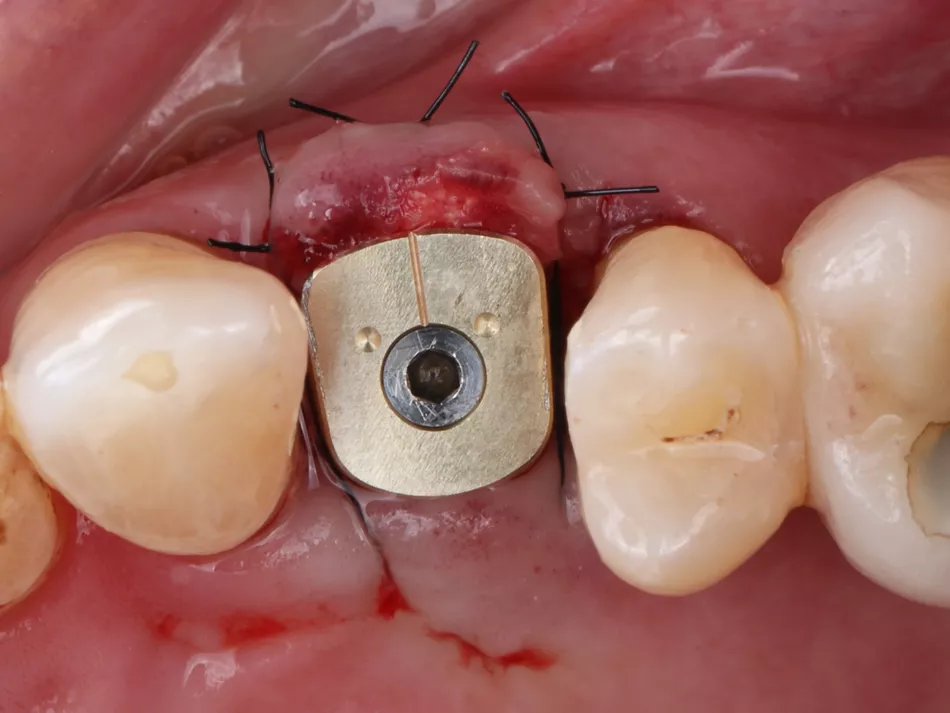

Phase IV: After a 2-month osseointegration period, delayed loading was initiated. A digital impression was captured directly on the Healfit® SH healing abutment acting as a scanbody, minimizing abutment disconnections and reconnections thus preserving peri-implant tissue integrity (Fig 5 a-d & 6).

The implant site was scanned (Straumann SIRIOS™ X3), and STL files were used to design a single crown on an X-Base® Ti-base (OPFLEX526). A long-term provisional crown was 3D-printed in resin, cemented extraorally, and delivered with adjusted occlusion for 6 months to monitor tissue stability and function (Fig 7-9) .

5a. 5b. 5c. 5d. Intraoral scan captured with Healfit® SH acting as a scannable healing screw.

5a

5b

5c

5d